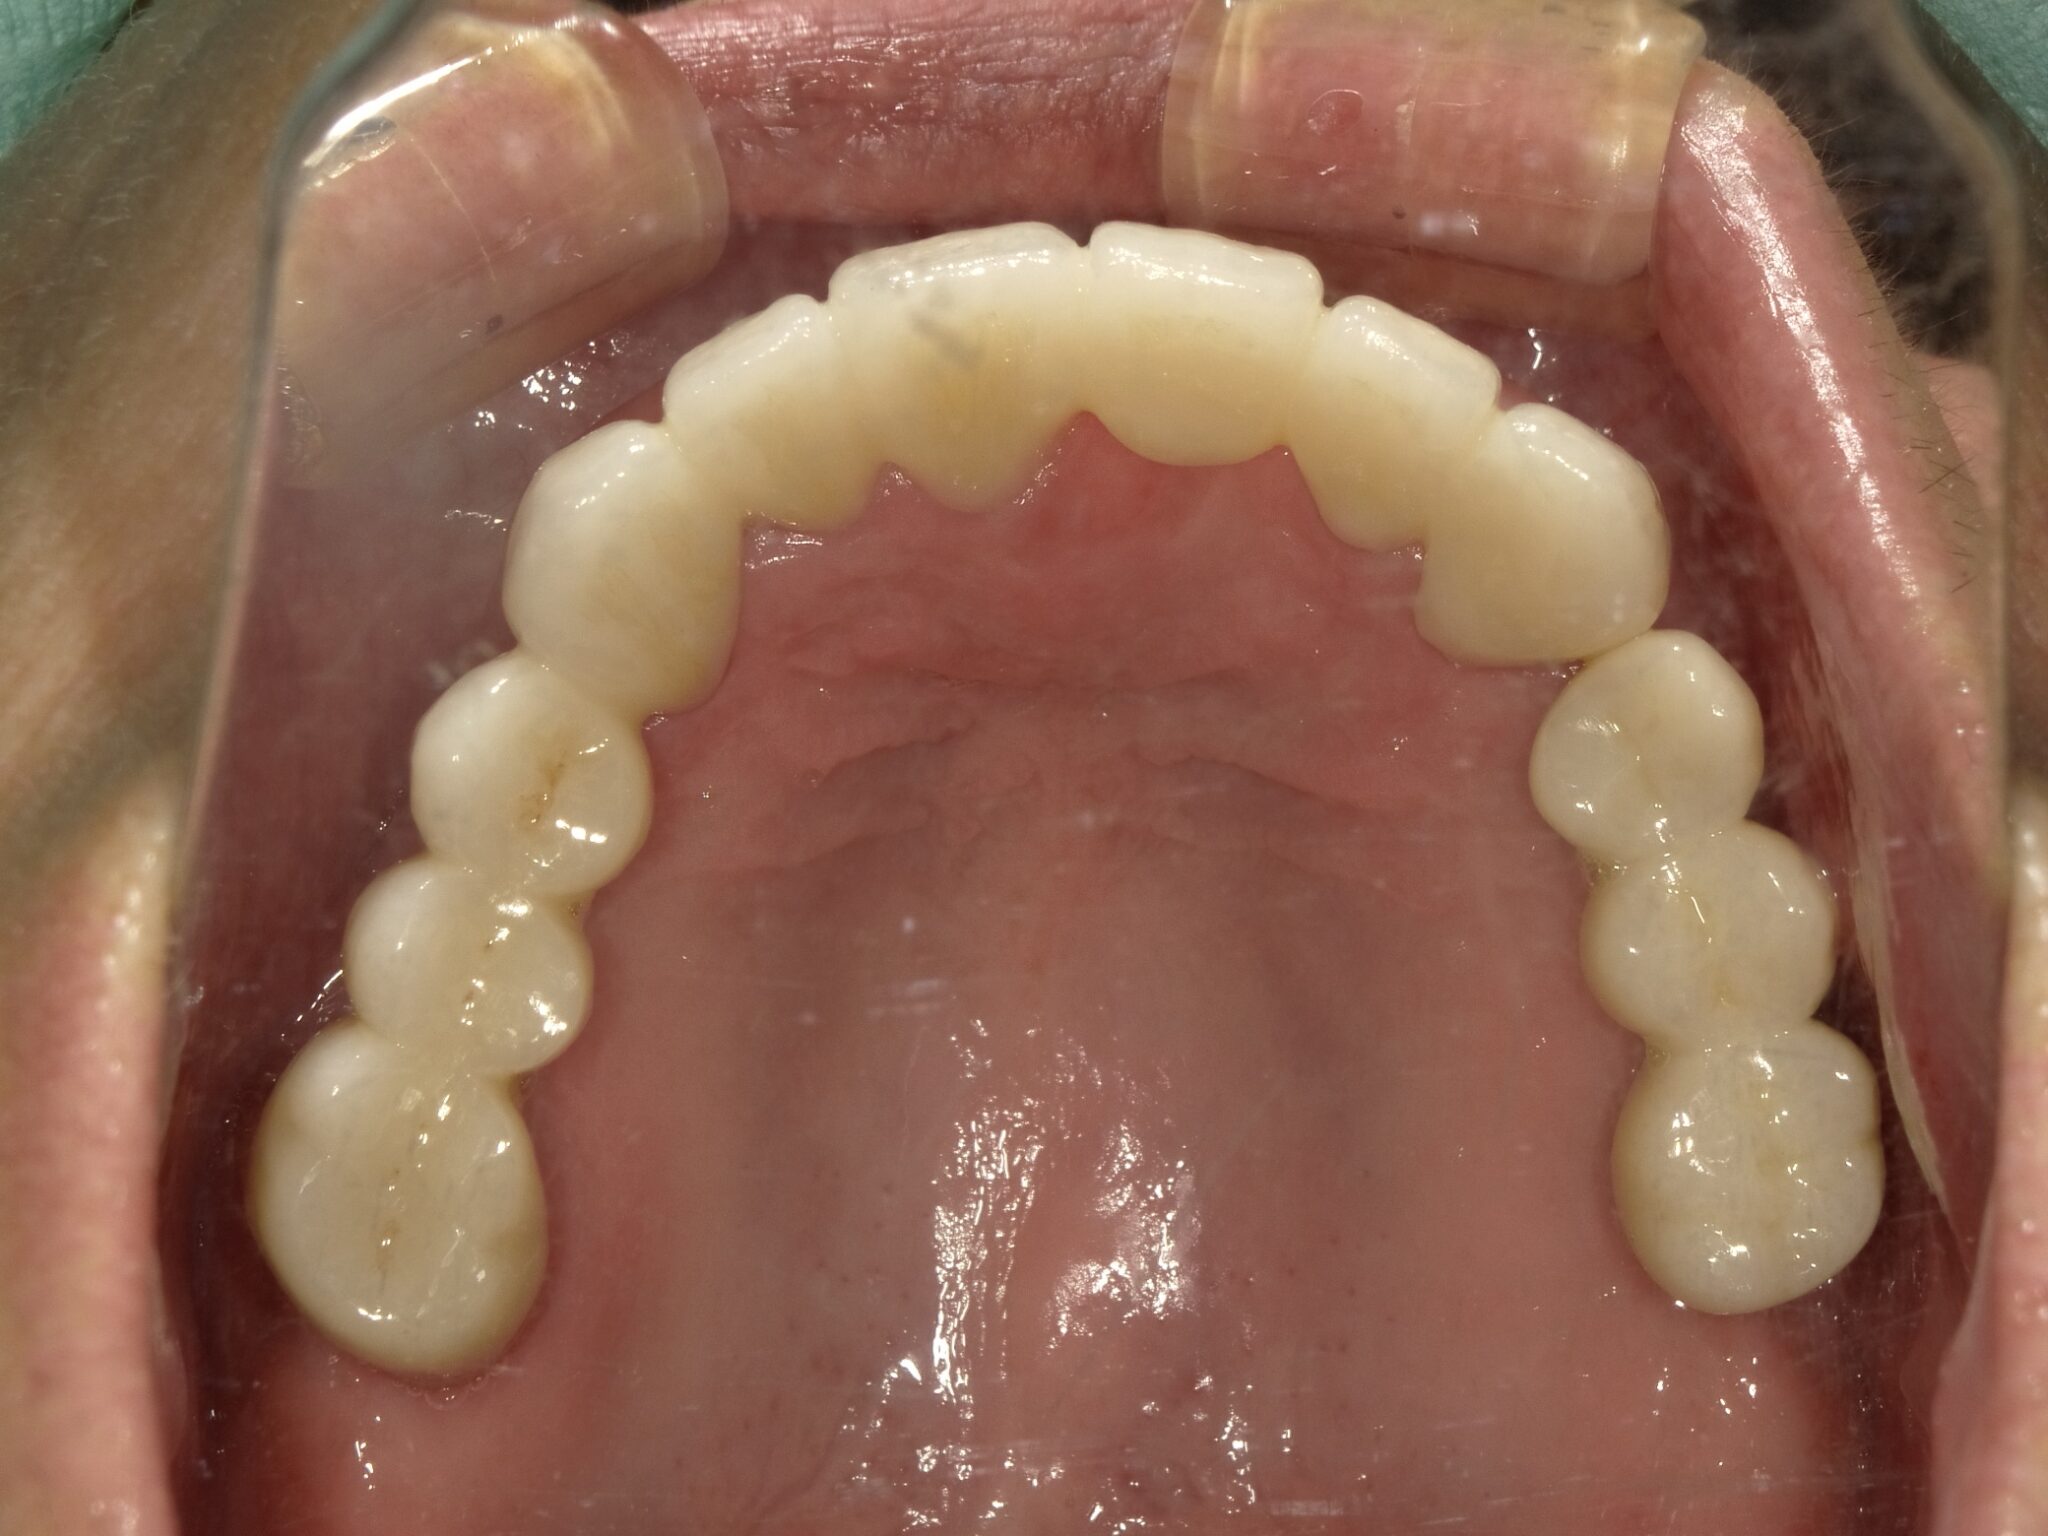

| 治療内容 | インプラント埋入(左下5・6,右下5・6,左上4・6) サイナスリフト(左上4・6) ジルコニアBr(右上6−左上3) E –MAX CAD(右下4) セラミックインレー(左下4) |